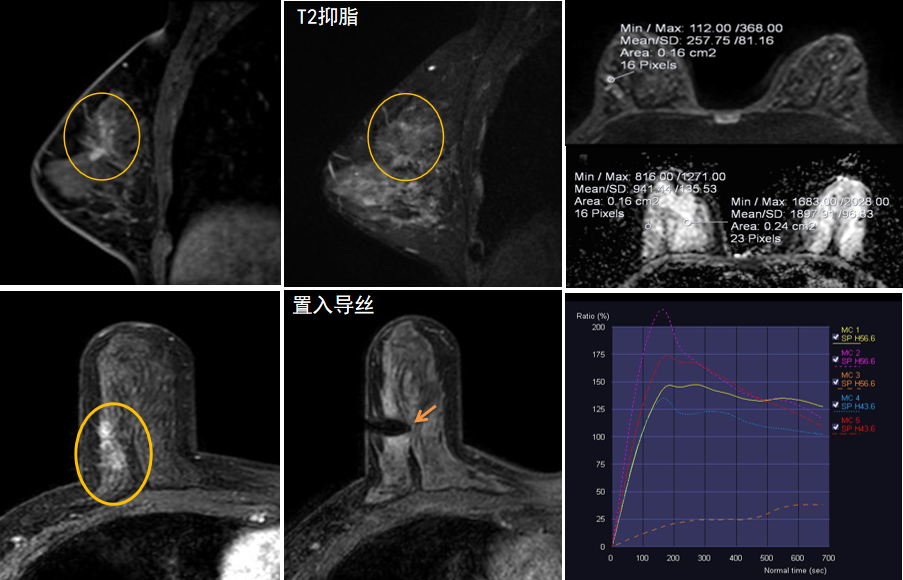

今年45歲的某女士,兩個(gè)月前行超聲檢查發(fā)現(xiàn)右乳結(jié)節(jié),乳腺X線攝影檢查提示右乳外上象限局部腺體結(jié)構(gòu)扭曲并簇狀無(wú)定形鈣化,為了進(jìn)一步評(píng)估病變性質(zhì)并確定范圍進(jìn)行了乳腺M(fèi)R平掃 DWI 增強(qiáng)的檢查,經(jīng)MR評(píng)估發(fā)現(xiàn)右乳病變范圍較廣,評(píng)估為BI-RADS 4類(lèi)可疑病變,需要取得病理學(xué)結(jié)果。

陳寶瑩主任及其帶領(lǐng)的MR介入診療小組詳細(xì)詢(xún)問(wèn)了病情,分析了患者資料,并與患者和臨床醫(yī)生進(jìn)行了充分溝通,確定于手術(shù)前為患者實(shí)施MR引導(dǎo)下的病變穿刺導(dǎo)絲定位和體表范圍確定。手術(shù)前陳寶瑩主任帶領(lǐng)聶品醫(yī)師、馬小偉技師、韓愛(ài)萍護(hù)士長(zhǎng)等MR介入診療小組成員,借助MR高清的圖像顯示和定位系統(tǒng),確定病變范圍,精準(zhǔn)穿刺置入定位導(dǎo)絲,并準(zhǔn)確標(biāo)記出病變體表范圍,整個(gè)過(guò)程患者無(wú)任何不適。在定位導(dǎo)絲和體表范圍標(biāo)記的輔助下,甲乳外科劉曉敏主任精準(zhǔn)切除了病變,解除了患者的后顧之憂(yōu)。

國(guó)內(nèi)外指南均建議40歲以上的女性每年行一次雙乳X線攝影(鉬靶)檢查,以篩查乳腺癌。對(duì)于乳腺癌高危人群40歲以前即建議開(kāi)始乳腺癌篩查,除了進(jìn)行乳腺X線攝影(鉬靶)篩查外需要補(bǔ)充MR檢查,MR檢查敏感性最高,能夠發(fā)現(xiàn)大量X線攝影和超聲檢查陰性的可疑病變,基于多模態(tài)、多參數(shù)的結(jié)構(gòu)和功能成像的基礎(chǔ)上,MR能夠精準(zhǔn)顯示病變位置、范圍以及病變內(nèi)的活性區(qū)域,MR引導(dǎo)下的介入診療不但解決了僅在MR顯示的病變的處置難題,而且能夠精準(zhǔn)定位活性區(qū)域,保證了定位、活檢及旋切的準(zhǔn)確性。